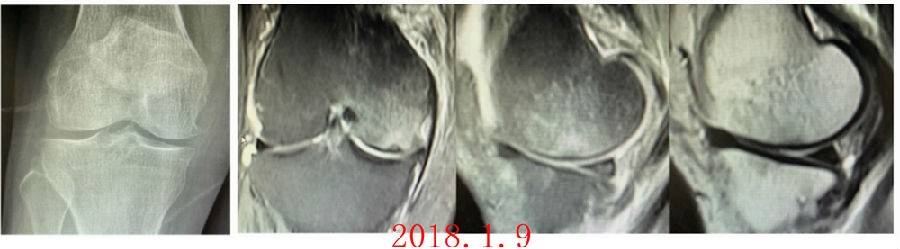

病例1:女,65岁,主诉右膝关节内侧疼痛1周。2018年1月X光未见右膝骨质异常,MR检查见股骨内侧髁骨坏死,半月板相对突出百分比(RPE)28.99%,关节线会聚角1.4°。

予切开行克氏针钻孔减压,口服消炎止痛药物、钙剂及骨化三醇,不负重6周,后改部分负重至3个月。2018年4月复查MR见骨髓水肿基本完全吸收,坏死区局限并修复良好,半月板相对突出百分比(RPE)32.08%,患者临床症状消失。